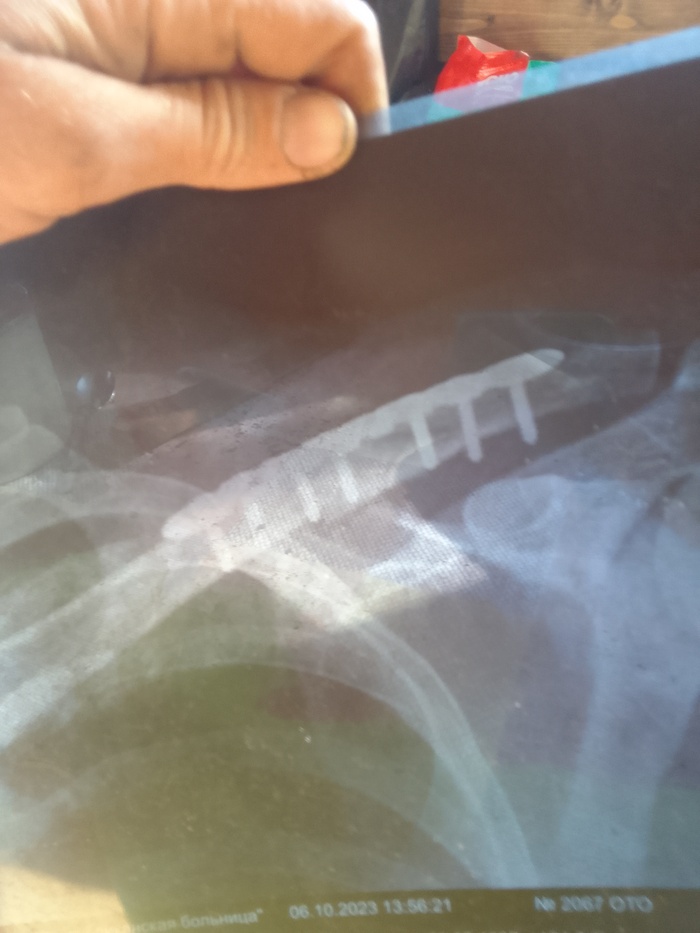

Всем привет. В общем и целом попал в дтп 24.09. (Мой апм совет не ездить на попутках). Собрали 4 встречных автомобиля,в 5-ю прилетел аккумулятор от нас.и разбил лобовое. Удар был в левый борт. Спасатели спилили крышу чтобы нас вытащить. Был за водителем слева. Сломано: шея, ключица, 3 ребра. Сотрясение мозга. 4 ушиба спинного мозга(позвоночника). Сидел я На пассажирском сиденье.был пристегнут. После аварии сделали 2 операции. 1. Вставили титановый межпозвонковый диск. 2 поставили плиту на левую ключицу из медицинской стали. Первую операцию делали через разрез на шее.по этому 1 месяц ел только детские пюре. Интервал между операциями 6 дней. Врачи сказали что Во время столкновения когда сломало шею, задело артерию. И кровью залило левое полушарие. В итоге была амнезия.сейчас все норм. Восстановился. Когла я окреп и воосстановился через 7 месяцев после дтп. Жена ушла от меня. Через 9 месяцев мы официально развелись по обоюдному согласию . С ней мы прожили без 3-х месяцев 10 лет. После развода. Прожили еще 10 дней. Она дала мне второй шанс. Но я неисправим. В итоге мы разошлись навсегда.живем сейчас по разным городам . Расстояние 3500 километров. Жизнь продолжается в новом ключе. У меня новая работа. Новая жизнь. Теперь живу один. Берегите себя и свою жизнь и цените то , что имеете. здоровье восстановилось все, кроме мозга. Алкоголь теперь под запретом. От слова совсем. Один раз попробовал . На утро 40 минут пытался вспомнить . Кто я и где я. Всем удачи в этой жизни и никогда не расстраивайтесь по пустякам. Я выжил. И я благодарен врачам за то что спасли. И жене(теперь уже бывшей) что выходила меня после аварии.

Плита на винтах. Будут вынимать 27.09